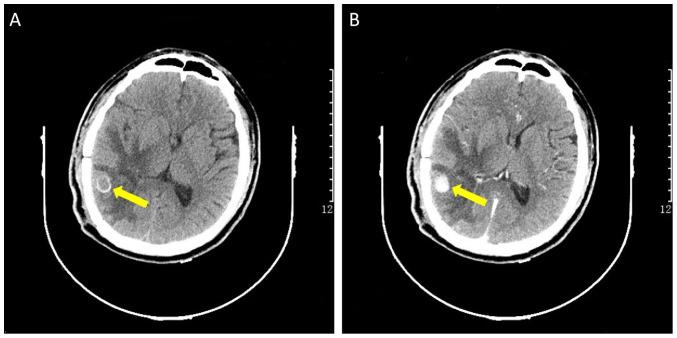

Intracranial infectious aneurysm (IIA) is one of the most severe complications of infective endocarditis (IE). Approximately 2-9% of patients with IE have IIA, which possibly results in severe neurological deficits. Currently, the most common treatment for IIA is endovascular treatment, while excision surgery is less common. The present study describes the case of a 33-year-old male patient who underwent a primary evacuation of an intracerebral hemorrhage (ICH) in the right temporal lobe. The patient was diagnosed with IE and IIA by examinations with an enhanced computed tomography scan, echocardiography and blood culture. In the recovery period after surgery, the patient suffered intracerebral rebleeding and underwent a surgery of IIA excision. The patient finally achieved a good prognosis without severe neurological dysfunction. In summary, IIAs are extremely rare entities, and a rare cause of spontaneous ICH. Previous research has demonstrated that the majority of ruptured IIAs receive endovascular treatment rather than conventional surgery. In the case presented herein, IIA surgical excision was successfully performed and complete pathological results were obtained, which has rarely been reported in the literature. The present case report reinforces the validity of traditional craniotomy according to the characteristics of IIAs.